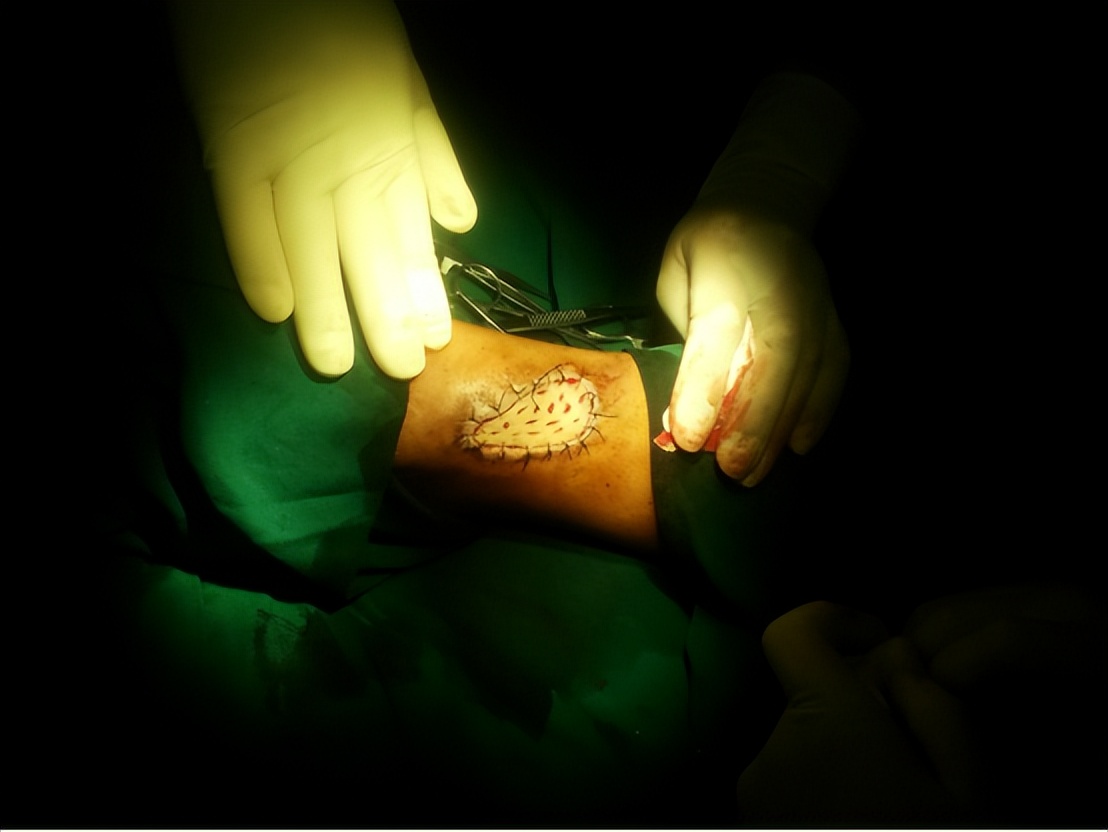

(6)皮瓣移植手术:皮瓣是含有皮肤、肌肉、血管以及神经等的复杂组织块。皮瓣常用于烧伤部位较深,可见肌肉、神经、血管及骨骼外露的部位,这些部位通过单纯的植皮无法愈合,通过进行皮瓣的移植,可以使烧伤部位的功能及美观得到较为理想的恢复。其他的皮肤移植手术方法包括邮票皮移植、自体表皮细胞培养移植等。